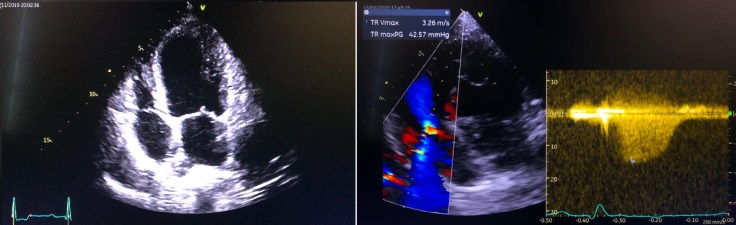

Per tale motivo l’esame idoneo a capirne l’origine è l’esame ecocardiografico. È un esame di durata variabile tra i 40 ed i 60 minuti, che solitamente si effettua sul cane sveglio, sdraiato su un apposito tavolino e permette di valutare il flusso sanguigno e i tessuti del cuore. A questo esame, su indicazione del Medico Veterinario che esegue la visita di approfondimento cardiologico, fa seguito un esame elettrocardiografico (comunemente chiamato ECG), per valutare la funzionalità elettrica del muscolo cardiaco e la presenza di eventuali aritmie concomitanti.